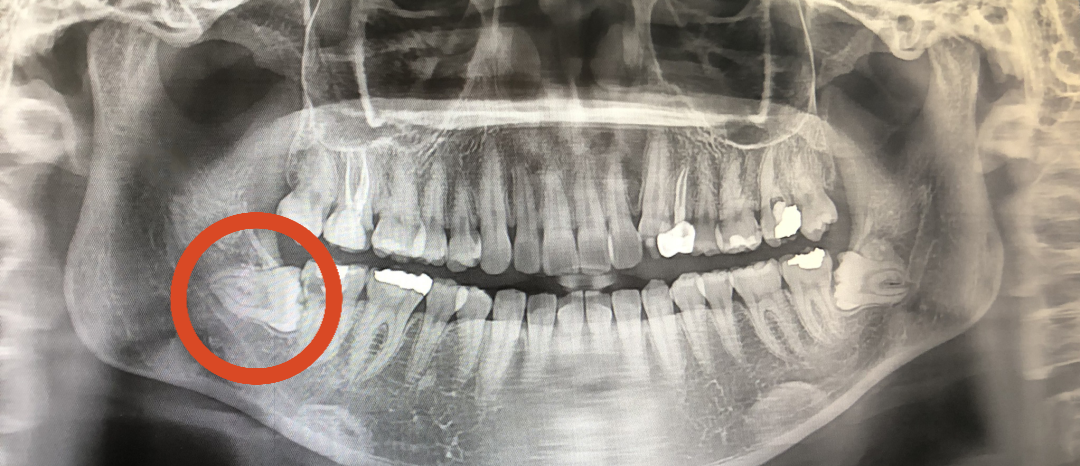

02. 3D-CT를 통해 사랑니의 크기와치아 방향, 깊이, 신경의 위치 확인

02. 3D-CT를 통해 사랑니의 크기와

치아 방향, 깊이, 신경의 위치 확인

사랑니가 나오는 방향, 위치, 각도가 올바르지 못해 통증과 붓기를 유발하여 불편함 초래

일상생활의 불편함사랑니가 나오는 방향, 위치, 각도가 올바르지 못해 통증과 붓기를 유발하여 불편함 초래